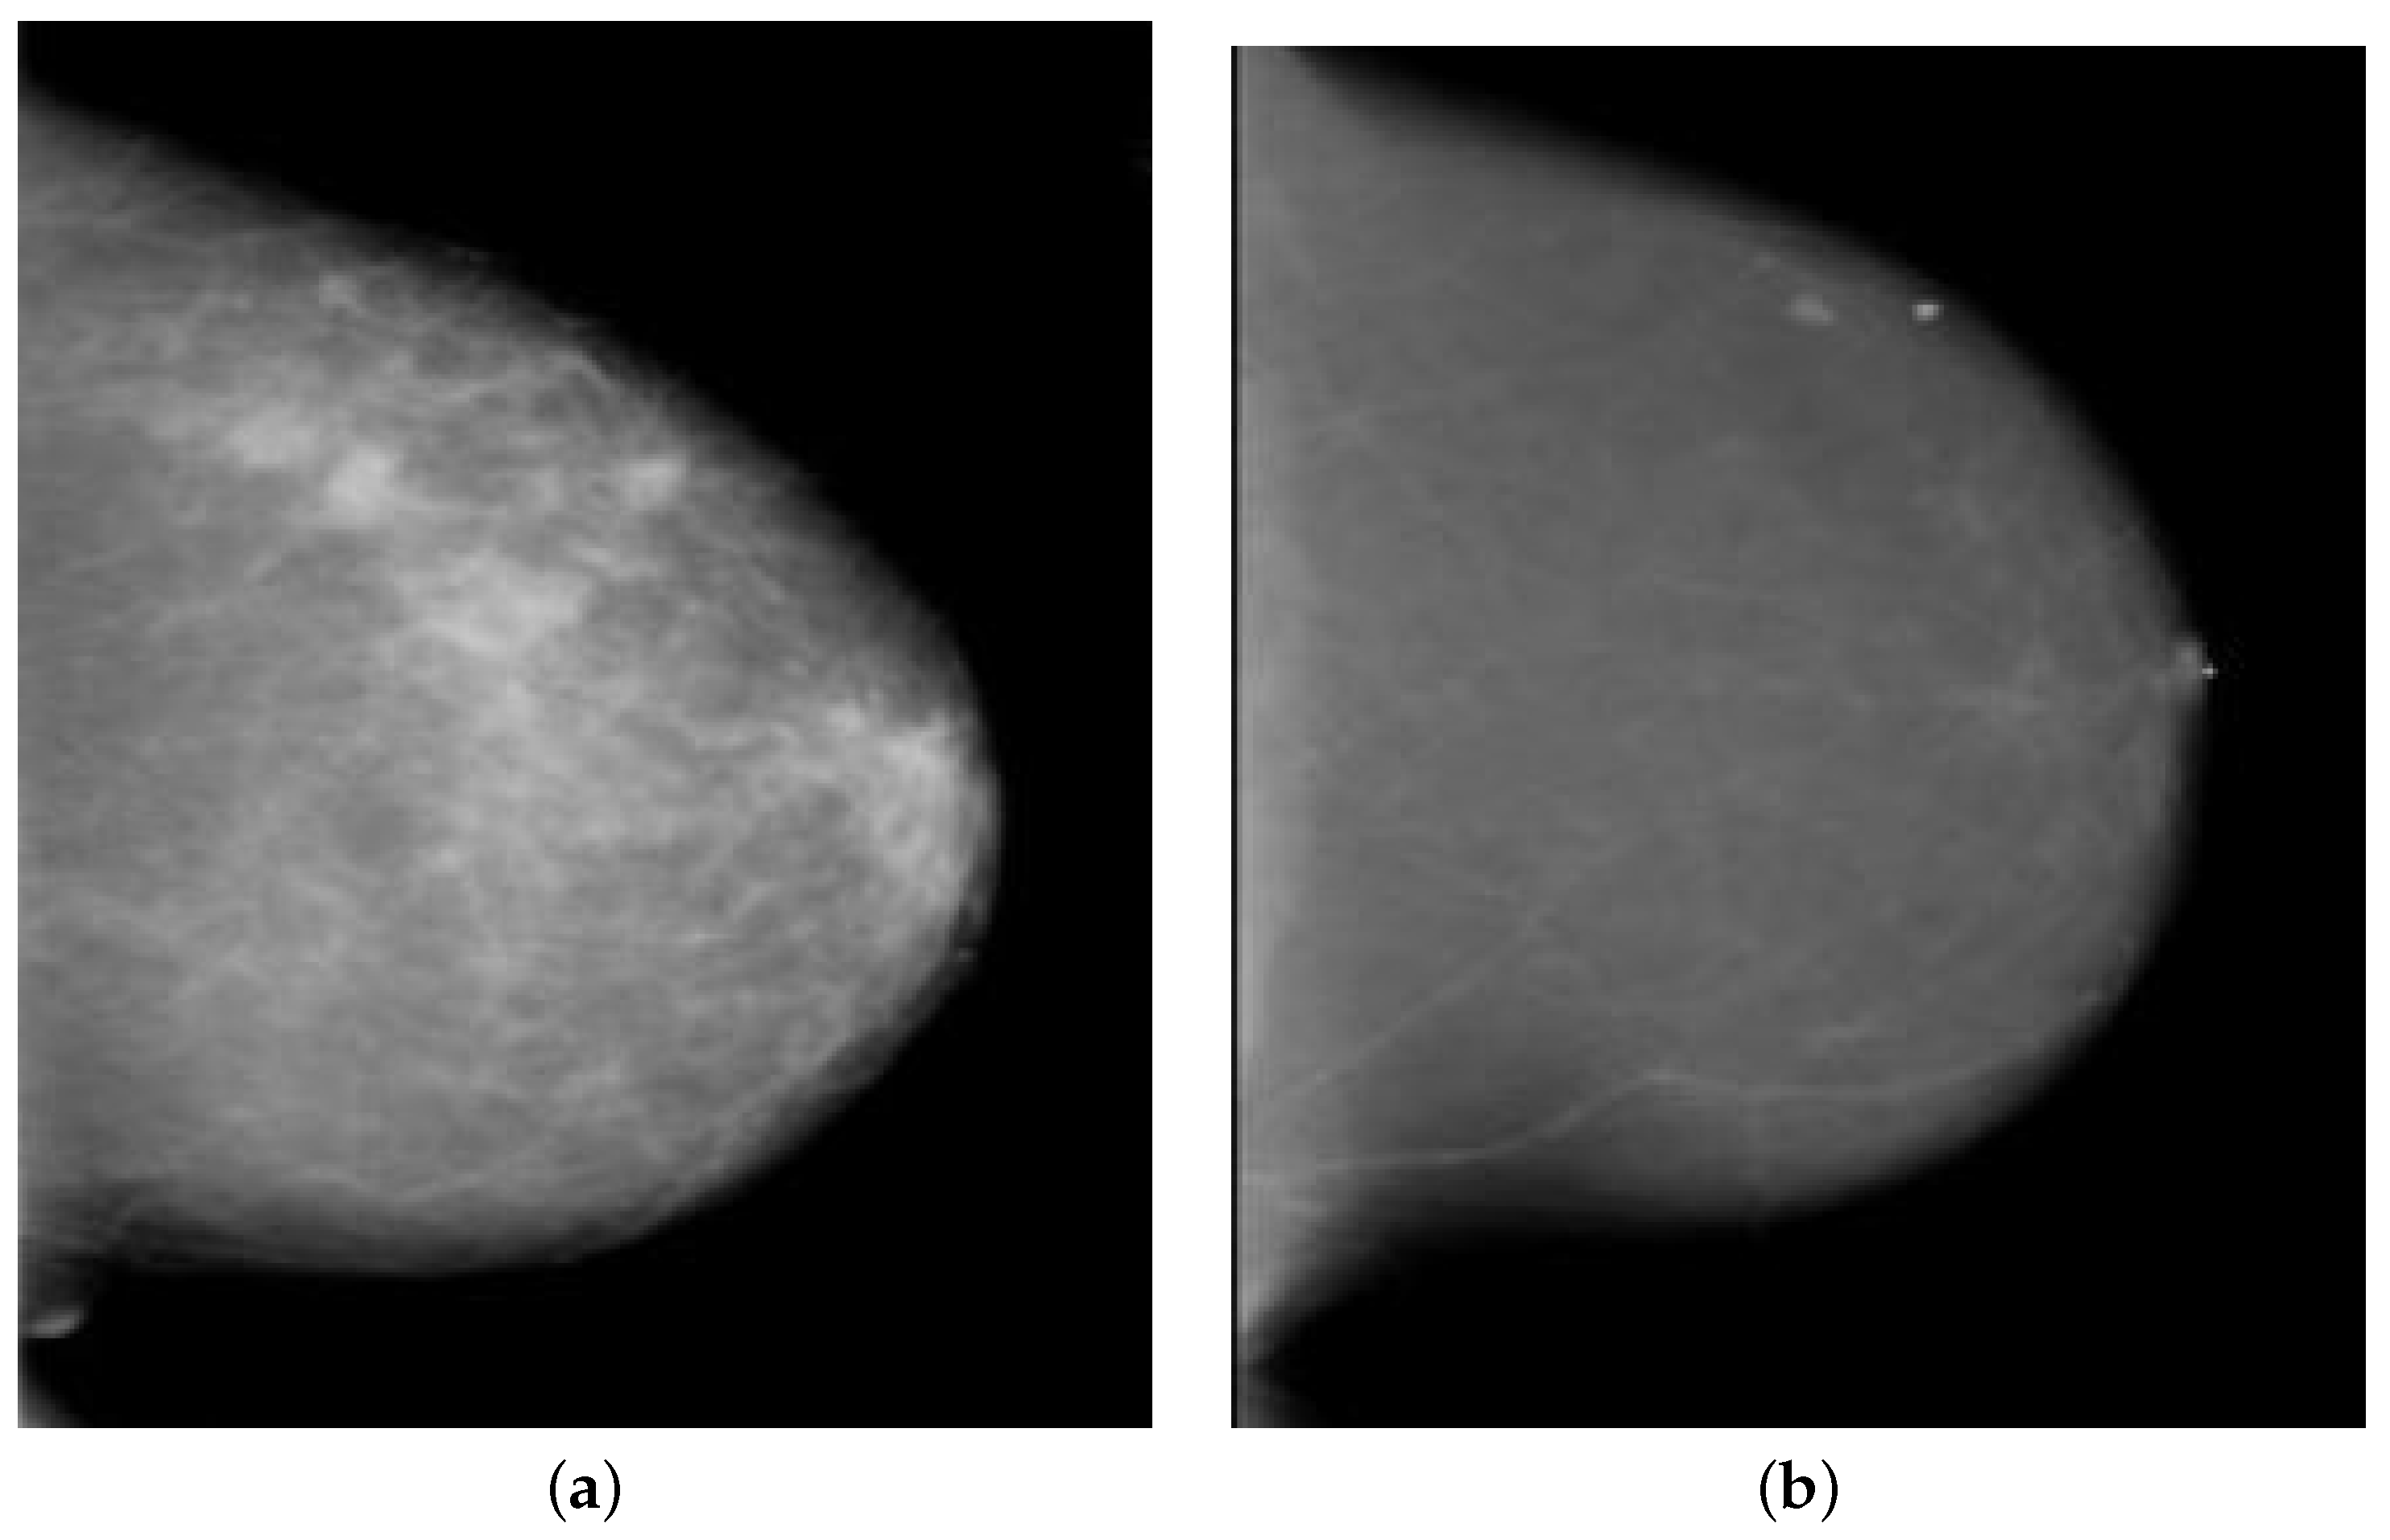

3.1. Dataset Description and Acquisition